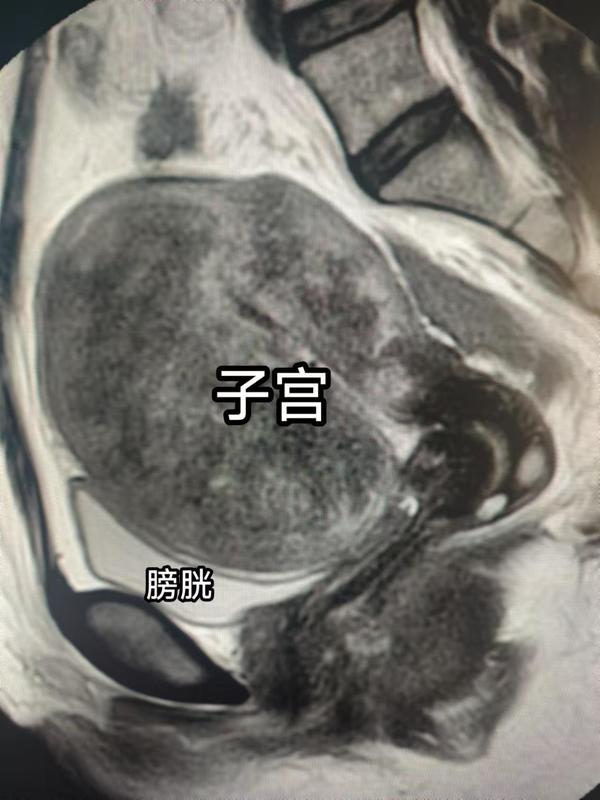

我不說(shuō),你絕對(duì)想不到這就是前天剛做完子宮全切手術(shù)的傷口。她前天做的手術(shù),明天就要出院了,你敢信?“什么?這不就是肚臍眼嗎?”沒(méi)錯(cuò),這就是肚臍眼,傷口就隱藏在肚臍眼內(nèi),毫無(wú)手術(shù)痕跡!這就是神奇的經(jīng)臍單孔腹腔鏡技術(shù)!不過(guò)她傷口能如此隱蔽還因?yàn)槲要?dú)門的,臍孔縫合技術(shù)!我也看過(guò)其他前輩們做的單孔腹腔鏡傷口,小紅書有見(jiàn)很多人曬傷口,不謙虛地說(shuō),全都沒(méi)我縫合的傷口好看!該患者是飽受子宮腺肌癥困擾的女性,出血、貧血、痛經(jīng),經(jīng)歷了漫長(zhǎng)的保守治療,最終下定決心來(lái)切除子宮。在手術(shù)之前,她還是非常擔(dān)心害怕的。但是手術(shù)的效果讓她非常地驚喜和意外。手術(shù)切除的標(biāo)本重達(dá)430g,正常子宮只有50~70g!下面是術(shù)前影像照片?子宮腺肌癥是一類以痛經(jīng)、月經(jīng)過(guò)多,和子宮逐漸增大為表現(xiàn)的子宮內(nèi)膜異位癥?;颊邥?huì)隨著子宮的不斷變大癥狀越來(lái)越重!輕度腺肌癥通常會(huì)選擇保守治療,打GnRHa針、口服地諾孕素、上曼月樂(lè)環(huán)等,目前非手術(shù)治療無(wú)根治辦法。而要解決根本問(wèn)題,只有切除子宮!我們的快速康復(fù)路徑,術(shù)前不喝瀉藥不灌腸,手術(shù)當(dāng)天可下地吃飯!出院速度自然是快的!對(duì)于重度腺肌癥患者,首選切除子宮!切除子宮,一身(生)輕松!